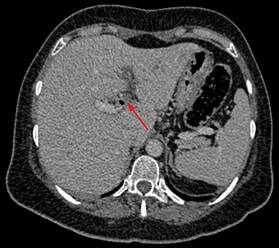

En el caso presentado, se observan datos de diverticulitis complicada a nivel de colon sigmoides, con trombo aéreo en vena sigmoidea adyacente y con extensión a vena mesentérica inferior (Figuras 1 y 2). Además, se visualiza defecto de llenado de la vena porta izquierda, secundario a trombo (Figura 3).